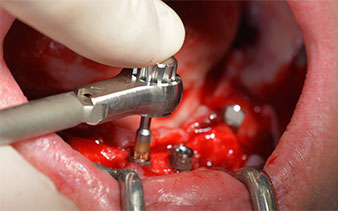

Le prochain réglage programmé est destiné à la mise en place des implants. Dans notre cabinet, nous appliquons généralement un couple de 32 Ncm pour cette phase (Fig. 12 et 13).

Contre-angle W&H

Fig. 12

Torque de 32 Ncm

Fig. 13

Une grande stabilité primaire est une exigence essentielle à la restauration immédiate. Pour s'en assurer, le forage n'a pas été taraudé ici. L'unit de chirurgie Implantmed W&H utilisé ici est doté d'un mode spécial adapté qui peut être directement sélectionné et est indispensable à de nombreuses indications. Lors du positionnement des implants, les derniers tours ont été effectués avec une valeur supérieure à 32 Ncm et ont été effectués à la clef à cliquet. Dans un tel cas, nous recommandons d'utiliser la fonction d'auto -taraudage de l'implant et de tourner plusieurs fois les implants vers l'arrière et vers l'avant.

Ceci permet à l'implant de s'approcher de la position finale progressivement sans exercer de pression excessive sur l'os (Fig. 14).

Implants

Fig. 14